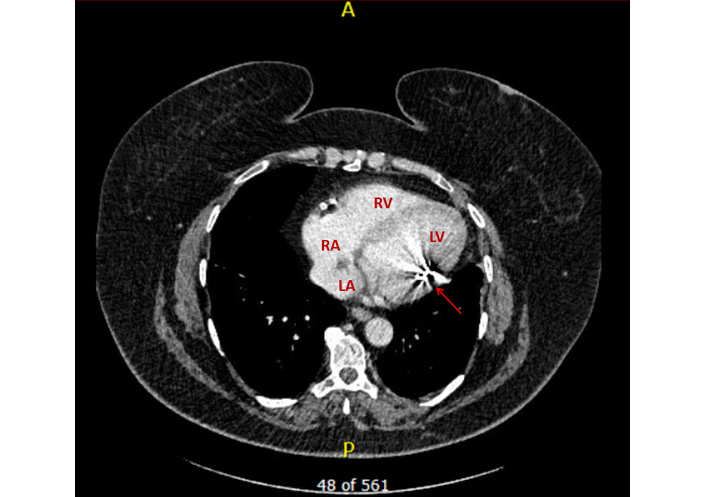

Computed tomography (CT) of the thorax confirmed the abnormal lead trajectory (Figure 5). Baseline laboratory investigations prior to the extraction, including renal function, electrolytes, and haematological parameters, are summarised in Table 1.

Computed tomography: crosssectional view demonstrating the ICD lead within the LV with metal artefacts (red arrow). ICD: implantable cardioverter defibrillator; LA: left atrium; LV: left ventricle; RA: right atrium; RV: right ventricle.